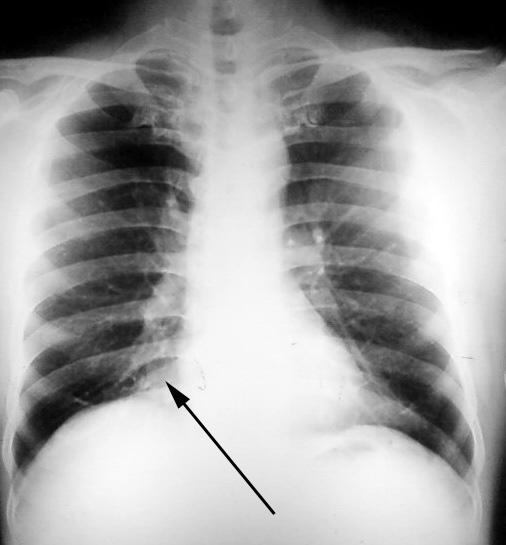

以下是引用yangzhenghai在2008-11-1 8:31:00的发言:[br]对,应该是脂肪垫。

以下是引用zhangzhongshou在2008-11-1 12:00:00的发言:[br]多可能为下腔静脉[br]